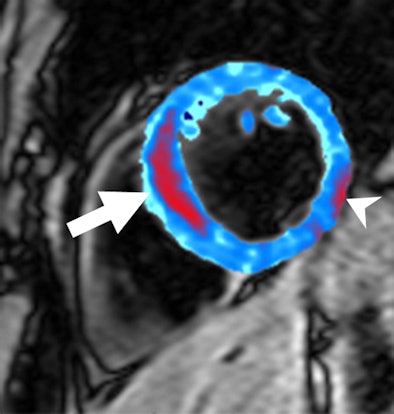

| Image of a left anterior descending artery occlusion acquired by T2-weighted MRI prior to contrast administration. Red area shows a region of postreperfusion hemorrhage (arrow). Susceptibility artifact adjacent to inferolateral epicardium was manually excluded (arrowhead). Image courtesy of the Medical Research Council Clinical Sciences Centre in London and Radiology. |

"Transmural edema was present in all subjects on the T2-weighted short inversion time inversion recovery images and was in the same anatomic region as the late gadolinium enhancement," the authors wrote.

The mean area of hemorrhage, as indicated by a T2 measurement of less than 20 msec, was 5% at the level of the infarct. The researchers set the 5% value of the hemorrhage area as the cutoff value for subsequent subgroup analysis. Six of the 15 patients demonstrated 5% or more hemorrhage after reperfusion.

By using a tone detection method, the mean ischemic area of risk in all subjects was 34% (range, 20%-57%). The researchers found that the mean ischemic area of risk was larger in subjects with 5% or more hemorrhage with a mean size of 44%, compared with 27% in subjects with less than 5% hemorrhage.